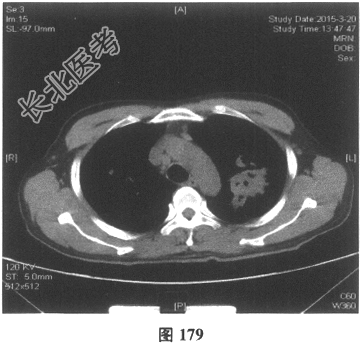

- [材料题] 患者男性,52岁,因间断发热伴咳嗽,咳少许黄痰,无咯血,伴胸闷憋气20余天就诊。体检:体温37.6~38.3℃。既往体健。查体:体温37.6℃,心率83次/分,呼吸20次/分,血压117/64mmHg。神志清,精神可,口唇无发绀;双肺呼吸音粗,可闻及广泛干、湿性啰音,以干啰音为主;心率83次/分,律齐,各瓣膜听诊区未闻及病理性杂音;腹软,无压痛及反跳痛,肠鸣音3次/分,双下肢无水肿。血常规检查:白细胞计数26.32×109/L,中性粒细胞0.846,血红蛋白117g/L,血小板计数1911×109/L;C反应蛋白119.05mg/L。尿常规检查:隐血2(+),蛋白1(+)。痰培养:曲霉菌属,请排除污染。生化全套检查:白蛋白19.6g/L,谷丙转氨酶24.2U/L,谷草转氨酶25.8U/L,γ-谷氨酰基转移酶91.4U/L;尿素氮13.00mmol/L(2.14~7.14mmol/L),肌酐166.8μmol/L(31~132μmol/L);血钾5.6mmol/L。肺部CT见图178~图185。

- 多项选择题4.[提示]患者应用多种抗生素治疗(第三代头孢菌素、青霉素加酶抑制剂)包括抗曲霉菌治疗无效,加用甲泼尼龙40mg静脉滴注病情好转。肺部CT检查显示病变明显改善。尿常规检查正常, 肾功能检测正常。复查肺部CT(图188~图195):示病变较前好转。Wegener肉芽肿的主要临床表现是( )